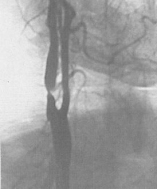

Ангиография – это наиболее точный метод, позволяющий увидеть на экране рентгеновской установки то, что происходит внутри сосуда (рис. 4). С него начинают, если пациент уже перенес инсульт и по данным УЗДГ МАГ выявлены значимо ограничивающие кровоток сужения сосуда, то есть высок риск повторения инсульта. Исследование проводится в специальной операционной, оснащенной ангиографической установкой.

Рис. 4. Критические стенозы внутренней сонной артерии (ангиография).

Во время ангиографии очень тонкий катетер вводится в артерию на ноге и продвигается к сосудам шеи. Место введения катетера будет обработано антисептиком и обезболено. После этого через катетер вводится контрастное вещество, делающее видимыми артерии, питающие мозг, под рентгеновскими лучами. Врач произведет съемку артерии. Если есть стенозы или окклюзии артерий – они будут обнаружены.

Рис. 4. Критические стенозы внутренней сонной артерии (ангиография).Во время ангиографии очень тонкий катетер вводится в артерию на ноге и продвигается к сосудам шеи. Место введения катетера будет обработано антисептиком и обезболено. После этого через катетер вводится контрастное вещество, делающее видимыми артерии, питающие мозг, под рентгеновскими лучами. Врач произведет съемку артерии. Если есть стенозы или окклюзии артерий – они будут обнаружены.